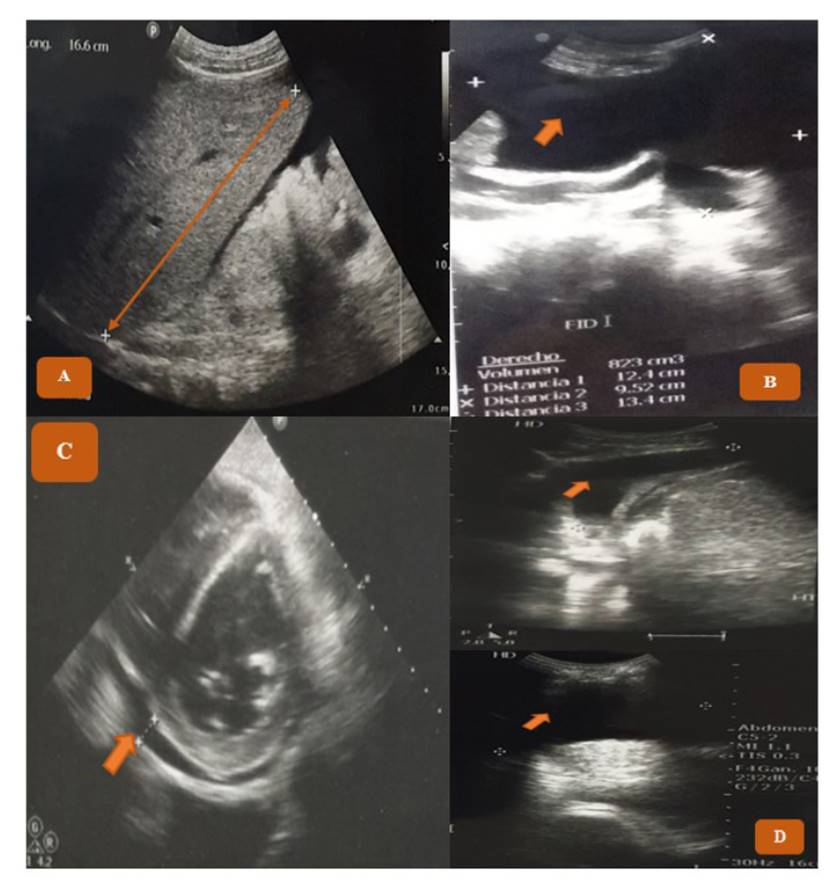

La TAC mostró un síndrome ascítico edematoso, hepatopatía crónica difusa; el ultrasonograma abdominal completo, hepatoesplenomegalia (Figura 1-A), poliposis vesicular y derrame pericárdico, además, muestra la presencia de ascitis (Figura 1-B); la ecocardiografía transtorácica, derrame pericárdico (Figura 1-C), y la ecografía de tórax (Figura 1-D), derrame pleural bilateral.

Figura 1 Ecografía abdominal completa muestra (A) Hepatomegalia (↔) : hígado con una longitud de 166 mm, y ascitis (→): líquido libre en cavidad abdominopélvica en la (B) fosa iliaca derecha (823 cm3). La ecocardiografía transtorácica muestra (C) derrame pericárdico (→); (D) La ecografía de tórax muestra derrame pleural bilateral (→): líquido libre en hemitórax derecho (140 cm3) y en hemitórax izquierdo (320 cm3)